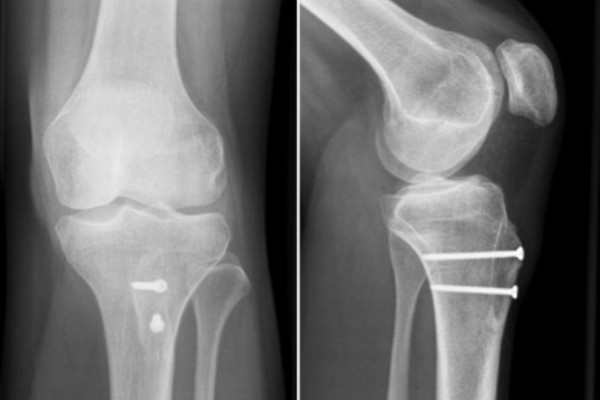

Hierfür wird der Sehnenansatz mit einem anhaftenden Knochstück vom Unterschenkelknochen gelöst und nach innenseitig verschoben bis die ausgemessene Fehlstellung korrigiert ist. Gleichzeitig kann bei diesem Eingriff auch die Höhe der Kniescheibe im Verhältnis zum Gelenkspalt korrigiert werden, indem der Sehnenansatz weiter in Richtung Fuß verschoben wird. Schließlich wird das abgelöste Knochenstück mittels 2- 3 Schrauben in der neuen Position fixiert. Hierdurch kommt es zu einer sicheren Ausheilung. Dieser Eingriff wird in der Regel mit dem Ersatz des MPFLs kombiniert.